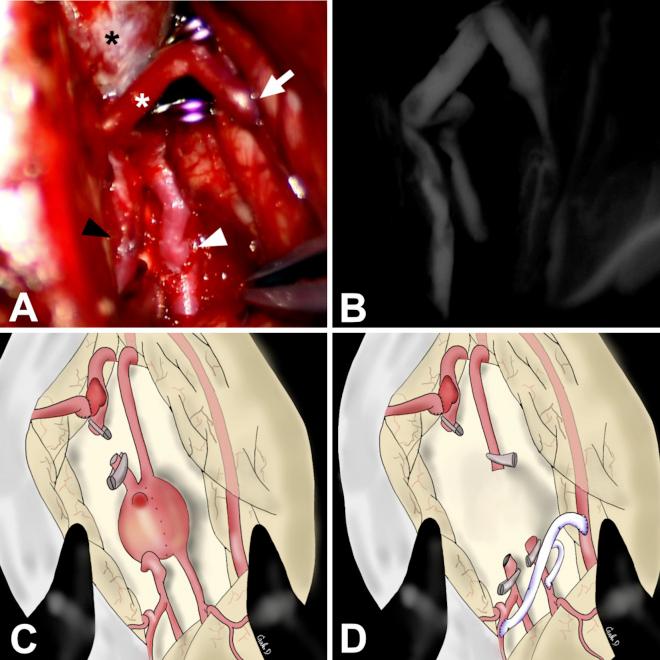

Rare case of de novo anastomotic site aneurysm after anterior cerebral artery side-to-side bypass: curative treatment with superficial temporal artery interposition graft-assisted trapping and etiological analysis. Illustrative case.

A 38-year-old-male first presented with a large fusiform aneurysm of the left distal ACA and underwent ACA-ACA STS bypass with aneurysm excision. Nonetheless, the de novo aneurysm was discovered to arise at the bypass site 7 months after the operation. Subsequently, a strategic radical intervention was performed. At the 26-month follow-up, the patient's modified Rankin Scale score was 0, and there was good bypass patency without aneurysm recurrence. The aneurysm formation was attributed to the fragility of the underlying arterial wall, which might be aggravated by STS bypass as evidenced by the histological findings and computational fluid dynamics (CFD) analysis.